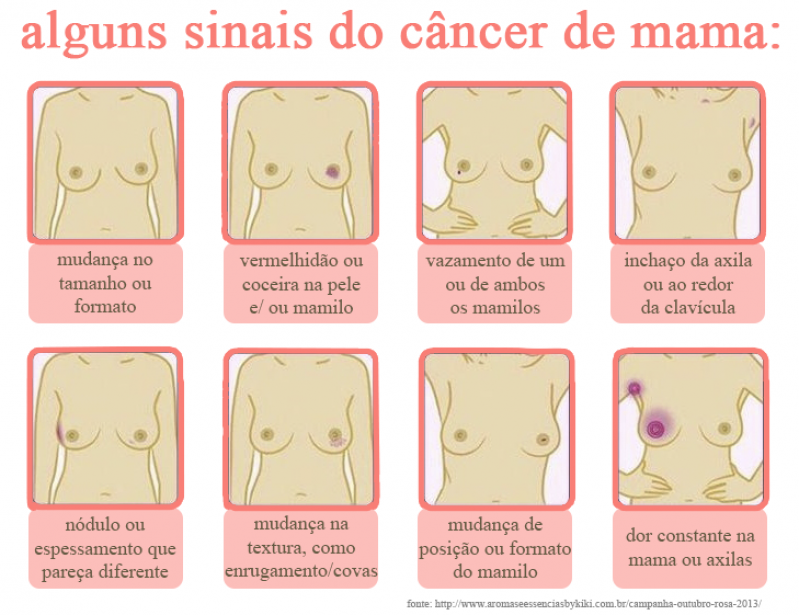

médico responsável pela mama perto Vila Congonhas tem como função principal prevenir, diagnosticar, tratar e reabilitar pacientes com câncer de mama. Uma vez que apenas o autoexame não é suficiente para perceber o surgimento de doenças o procedimento deve ser realizado por um profissional. Com isso, é possível garantir qualidade e eficiência no diagnóstico e tratamento.